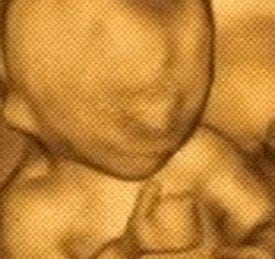

エコーを担当されていた助産師さんのリアクションを尋ねると「手をグーパーグーパーしてからグッジョブしてくれたので『可愛いですねぇ〜』と言ってくれました」と明かす@58vfw214さん。

こんなこっち向いてファンサしてくれる事ある?よく見たらグッジョブしてるし👍

お前…さては陽キャだな??? pic.twitter.com/aovkvtmI3Q